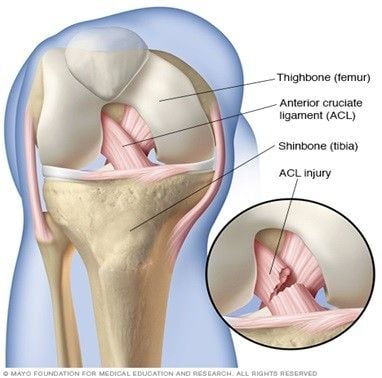

Hình 1: Giải phẫu 2 bó dây chằng chéo trước

Về mặt giải phẫu dây chằng chéo trước gồm 2 bó là: bó trước trong và bó sau ngoài. Bó trước trong là bó chính có tác dụng giữ vững gối khi gấp, bó sau ngoài là bó phụ có tác dụng giữ vững gối khi duỗi.